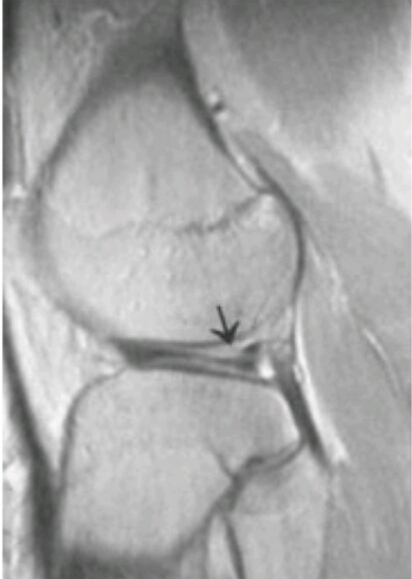

Name the problem.

medial meniscus tear